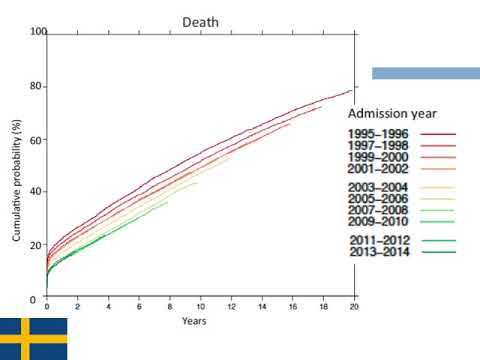

Una década de ablación de arritmias cardiacas en Suecia. Dra. Carolina Reynoso. Residencia de Cardiología. Hospital C. Argerich. Buenos Aires

La mejoría en los resultados en IAMCEST- registro SWEDEHEART. Dra. Sofía Gabriela Rodríguez. Residencia de Cardiología. Hospital C. Argerich. Buenos Aires